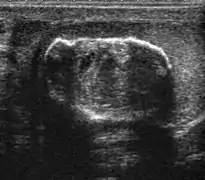

Sonography of a normal testis. The normal testis presents as a structure having homogeneous, medium level, granular echotexture. The mediastinum testis appears as the hyperechoic region located at the periphery of the testis as seen in this figure.

The normal adult testis is an ovoid structure measuring 3 cm in anterior-posterior dimension, 2–4 cm in width, and 3–5 cm in length. The weight of each testis normally ranges from 12.5 to 19 g. Both the sizes and weights of the testes normally decrease with age. At ultrasound, the normal testis has a homogeneous, medium-level, granular echotexture. The testicle is surrounded by a dense white fibrous capsule, the tunica albuginea, which is often not visualized in the absence of intrascrotal fluid. However, the tunica is often seen as an echogenic structure where it invaginates into the testis to form the mediastinum testis. In the testis, the seminiferous tubules converge to form the rete testes, which is located in the mediastinum testis. The rete testis connects to the epididymal head via the efferent ductules. The epididymis is located posterolateral to the testis and measures 6–7 cm in length. At sonography, the epididymis is normally iso- or slightly hyperechoic to the normal testis and its echo texture may be coarser. The head is the largest and most easily identified portion of the epididymis. It is located superolateral to the upper pole of the testicle and is often seen on paramedian views of the testis. The normal epididymal body and tail are smaller and more variable in position.